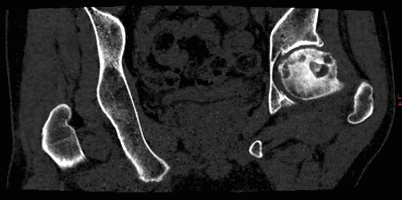

病例1:髋关节4D成像。Revolution CT 采用16cm探测器覆盖范围的连续扫描即可得到关节动态图像。此临床应用目的为鉴别撞击综合症和股骨头坏死。